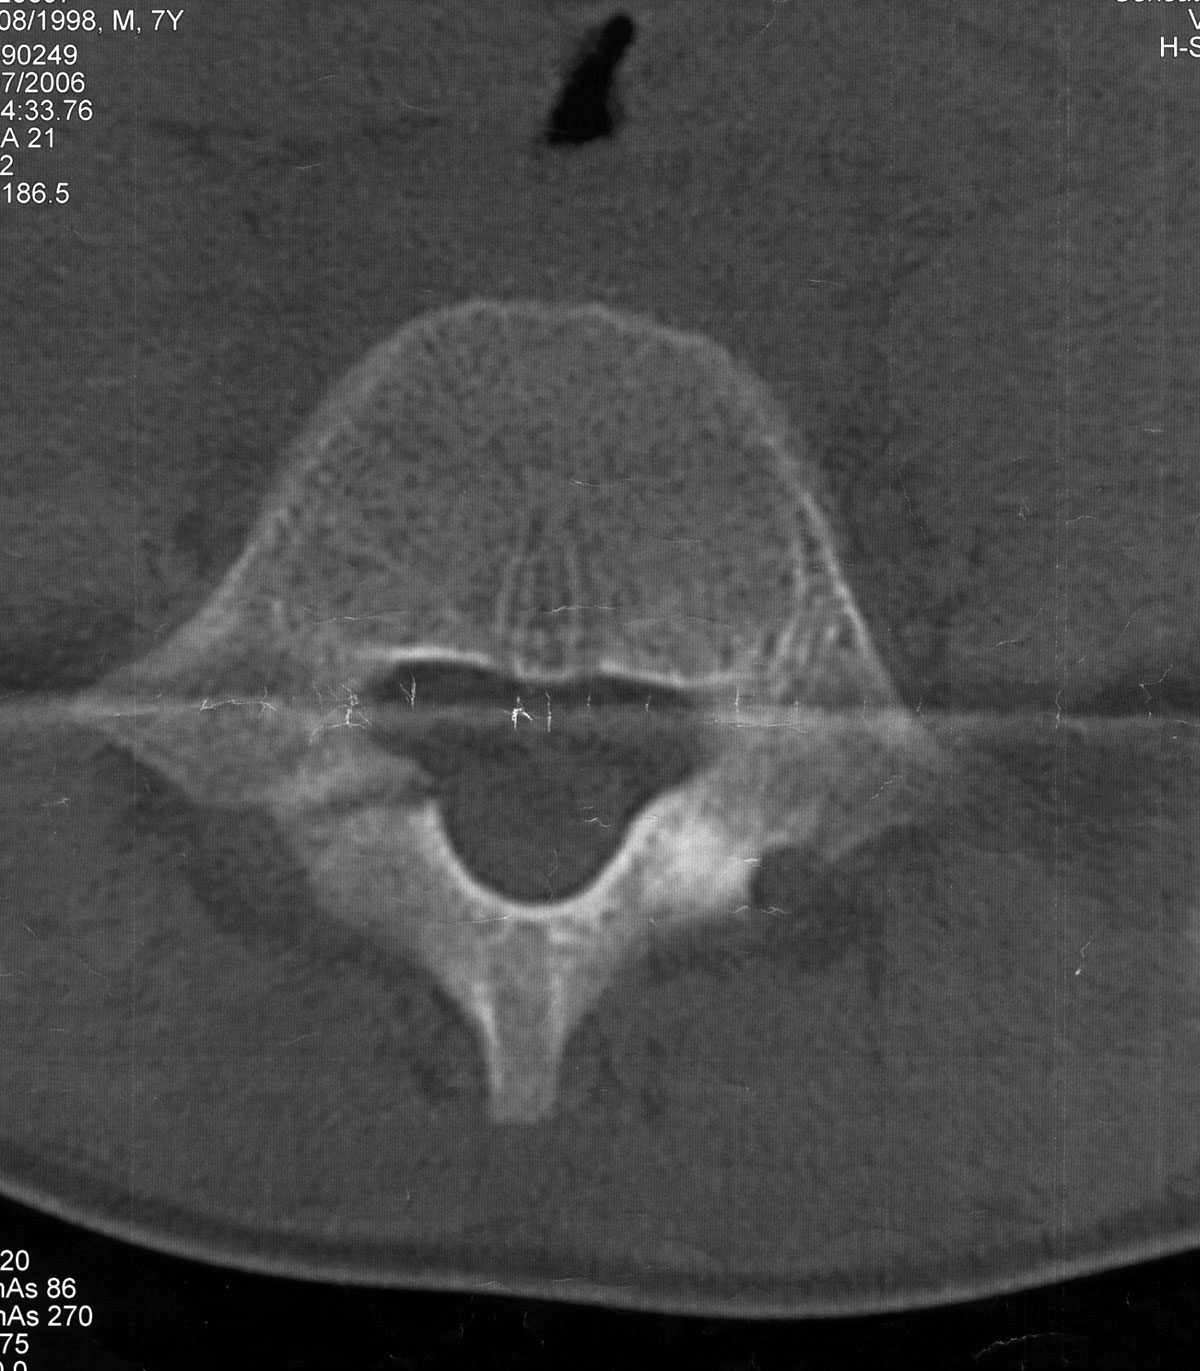

Eine Alternative stellt die Dünnschicht-CT des betroffenen Wirbelkörpers dar. Es ist auf eine entsprechende Gantry-Kippung zu achten, um diese Spondylolyseregion orthograd zu treffen (Abb. 2b + 3). Eine Kernspintomographie kann ebenfalls dienlich sein, hier finden sich typischerweise bone-bruise-artige Veränderungen in den T2- und STIR-Wichtungen, die Unterbrechung in der Interartikularportion ist jedoch kernspintomographisch nur schwierig zur Darstellung zu bringen (Abb. 2a). Die Kernspintomographie stellt am besten den Degenerationsgrad des betroffenen Bandscheibenfaches und mögliche neuroforaminale Engen dar. Der diagnostische Algorithmus sollte somit primär eine konventionelle Röntgenaufnahme in 2 Ebenen beinhalten. Bei anhaltenden Beschwerden ist eine Kernspintomographie und bei fehlendem Nachweis eines Korrelates für die bestehende Symptomatik eine Dünnschicht-CT zum Nachweis oder Ausschluss der Spondylolyse indiziert. Eine Drei-Phasen-Skelettszintigraphie oder ein SPECT/CT können in Ausnahmefällen ebenfalls als diagnostisches Mittel Einsatz finden, sollten jedoch aufgrund der Strahlenbelastung nur in ausgewählten Fällen zum Einsatz kommen.